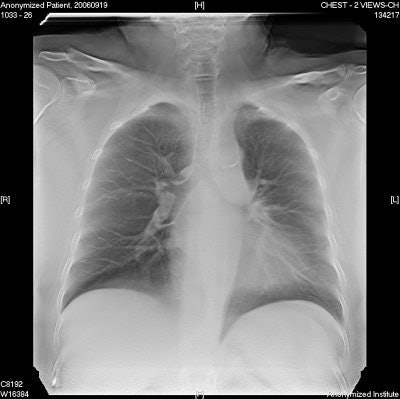

![]() |

| Chest image taken with GE's VolumeRAD tomosynthesis software. Image courtesy of GE Healthcare. |